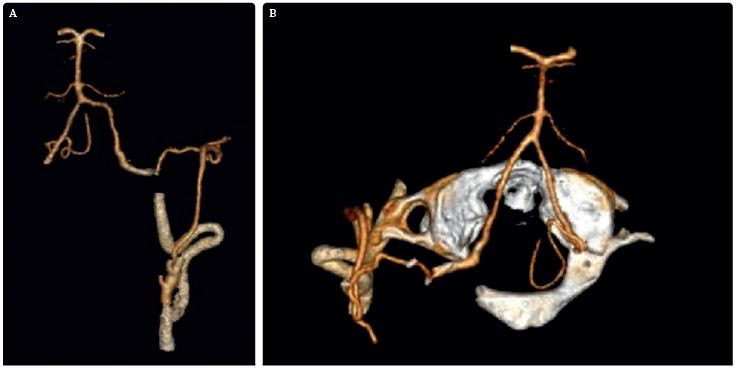

Na zobrazení MR DW (MR obraz s difuzním vážením) byly patrné čerstvé ischemické změny v dolní části levé mozečkové hemisféry v teritoriu PICA (arteria cerebelli inferior posterior) vlevo, a dále v bazi levého brachium pontis. Drobné změny jsou i v teritoriu horní mozečkové tepny vlevo a drobný okrsek restrikce MR DW v dolním okraji pravé mozečkové hemisféry v teritoriu PICA vpravo (obr. 1). Na CTA (výpočetní tomografie – angiografie) a DSA (digitální subtrakční angiografie) byl patrný uzávěr odstupu obou vertebrálních arterií (obr. 2). Zadní mozkové řečiště, tzn. bazilární tepna (BA), PCA a distální části vertebrálních tepen, se plnilo retrográdně cestou zadních komunikant (obr. 3). Retrográdní tok v levé a. vertebralis dosahoval až do extrakraniálního úseku V3 v oblasti oblouku prvního krčního obratle C1 (obr. 4). Nová vyšetřovací modalita QMRA prokázala retrográdní tok v levé zadní komunikantě 30 ml/min a sotva detekovatelný retrográdní tok v bazilární arterii 17 ml/min (obr. 5).

Ze zobrazovacích vyšetření vyplývá, že nemocný má nedostatečnou perfuzi ve VB povodí. Podle studie Veritas jde o „low flow“ pacienta s ročním rizikem opakovaného iktu 22 %.1,2 U těchto pacientů je indikován revaskularizační výkon. Endovaskulární rekanalizace chronického uzávěru vertebrálních tepen nebyla možná, proto jsme se rozhodli provést augmentaci průtoku ve VB povodí pomocí bypassu okcipitální arterie (z povodí a. carotis externa) na horizontální segment vertebrální arterie V3 vlevo. Tímto bypassem jsme plánovali posílit průtok ve vertebrální arterii bypassem z povodí karotidy, obnovit znovu antegrádní tok v bazilární tepně a normalizovat průtok ve VB povodí.